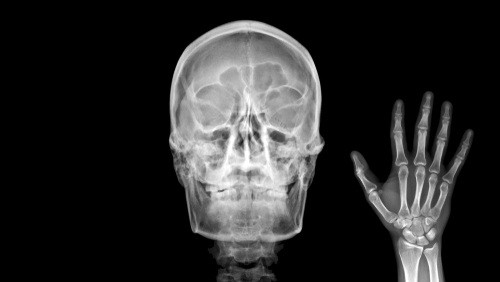

Фотогалерея

Рентген-аппарат